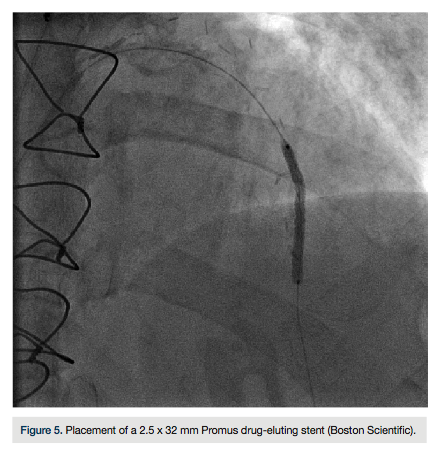

Given the angiographic findings, we elected to use a Rotablator (Boston Scientific) to facilitate stent delivery. A Runthrough wire (Terumo) was advanced and exchanged distally through an over-the-wire balloon for a Rota floppy wire (Boston Scientific). A 1.25 mm burr was used to perform rotational atherectomy (Figure 4). The wire was changed out to a

Wiggle wire (Abbott Vascular) and then we predilated with a 2.5 x 15 mm Angiosculpt (AngioScore) balloon. A 2.5 x 32 mm Promus drug-eluting stent (Boston Scientific) was advanced, covering the entire lesion length, and deployed at 12 atmospheres, then re-inflated to 14 atmospheres (Figure 5). Final angiography revealed TIMI-3 flow. The patient became bradycardic and subsequent repeat angiography demonstrated distal embolization to the apical LAD with loss of distal branches. She was given an intracoronary eptifibatide (Integrilin, Millenium Pharmaceuticals) bolus. Repeat angiography demonstrated recovery of flow in the apical branch (Figure 6). The patient tolerated the procedure well and was asymptomatic